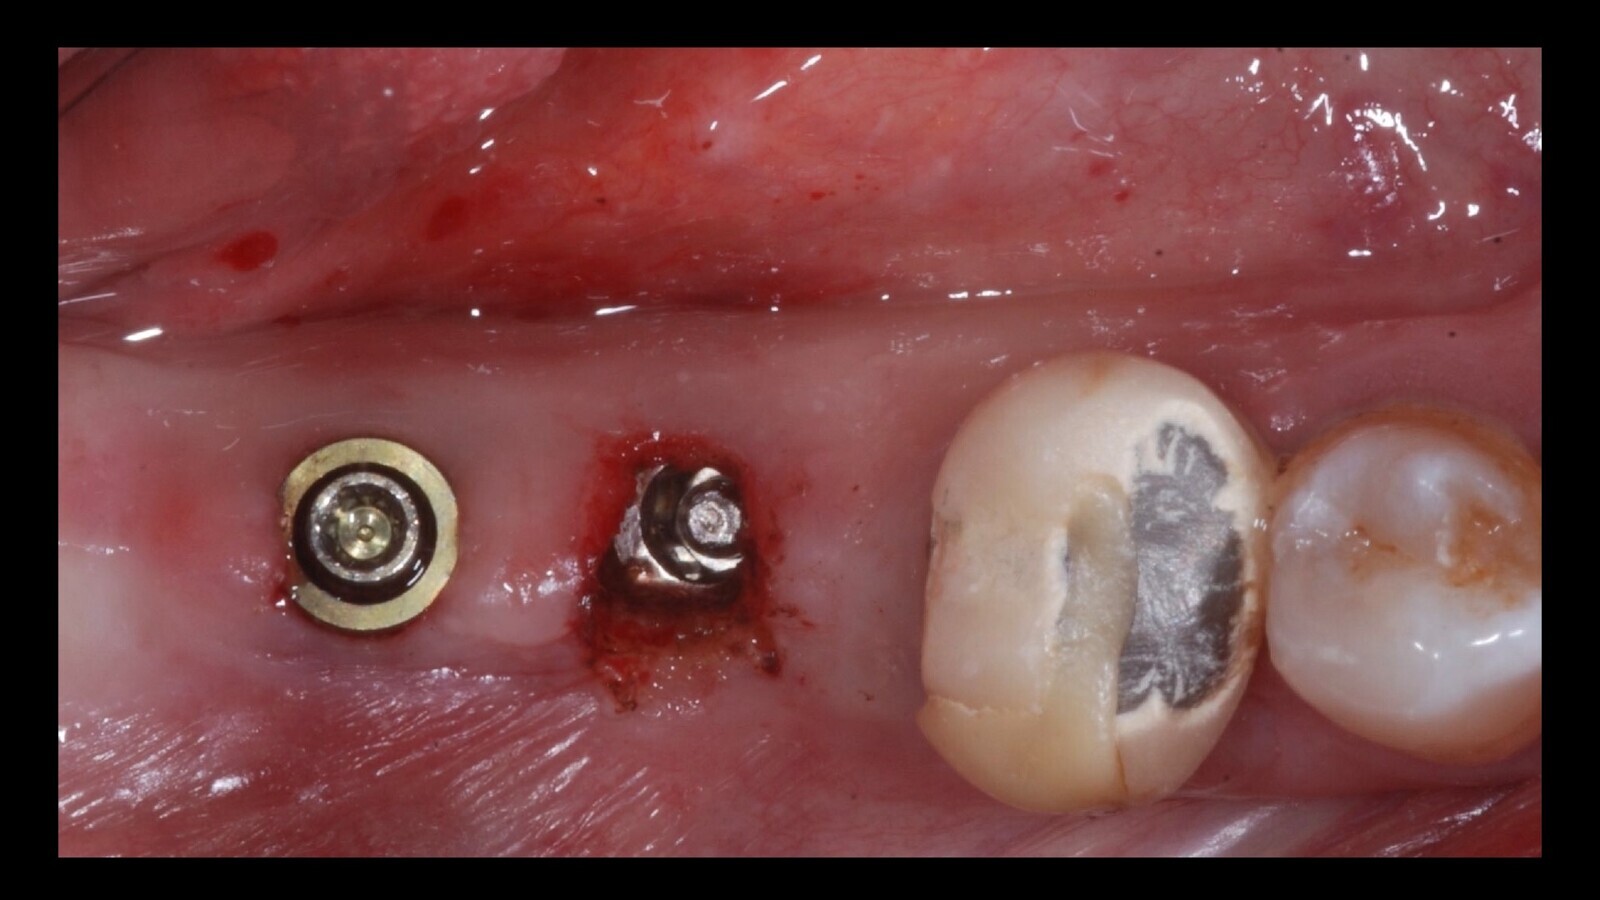

Figura 1. El examen intraoral mostró que los túneles gingivales estaban completamente cerrados (a) para la regeneración del tejido (b), confirmando el tiempo transcurrido desde que se desatornillaron.

Figura 2. La presencia de un solo tornillo con la cabeza con el encaje para el destornillador y la integridad del relleno del orificio de acceso oclusal en el elemento 4.6 sugería que el segundo tornillo estaba fracturado. De lo contrario, el artefacto protésico no podría haberse desprendido.